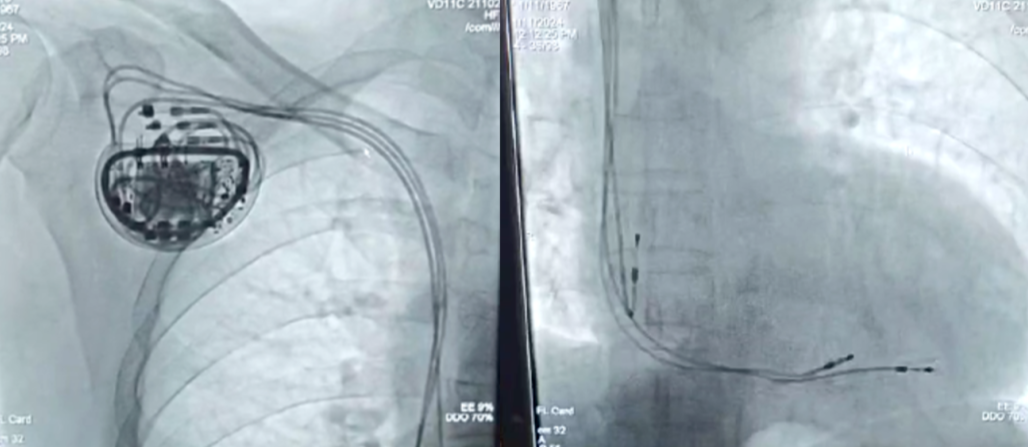

经过全面的术前准备,华伟教授、曹克将教授团队的顾凯教授和合肥高新心血管病医院刘亮主任等密切配合,凭借丰富的手术经验成功在右心耳处植入一根被动电极,分别在右心室室间隔前部和右心室间隔后部植入两根主动电极,术中测试心室电极1:阈值0.7V,电极阻抗760Ω,R波幅度>16mV;心室电极2:阈值1.2V,电极阻抗640Ω,R波幅度>15mV;心房电极:起搏阈值0.5V,电极阻抗680Ω,P波幅度>7.0mV,经测试植入体内的调节器各项参数良好,电极精准植入到合适的心肌部位。

术后造影

CCM植入术后短期效果评估:术后3小时的心超检查显示LVEF 42%,LVDD 62mm;术后24小时的心超检查显示LVEF 43%,LVDD 62mm;术后7天的心超检查显示LVEF 44%,LVDD 61mm。主要研究者曹克将教授和华伟教授表示:短期观察发现,患者接受CCM治疗后LVEF提高,心功能逐渐改善。目前该研究小组对患者的临床心功能与植入CCM后的相关参数正在进行密切随访。